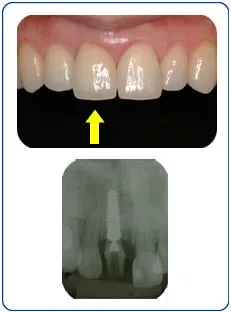

インプラント治療例02 30代女性 右上中切歯インプラント審美治療

Before

After

根の病気により抜歯を行い、骨造成術(GBR)や軟組織造成術(上皮下結合組織移植術)などのテクニックを用いてインプラントの審美修復を行いました。